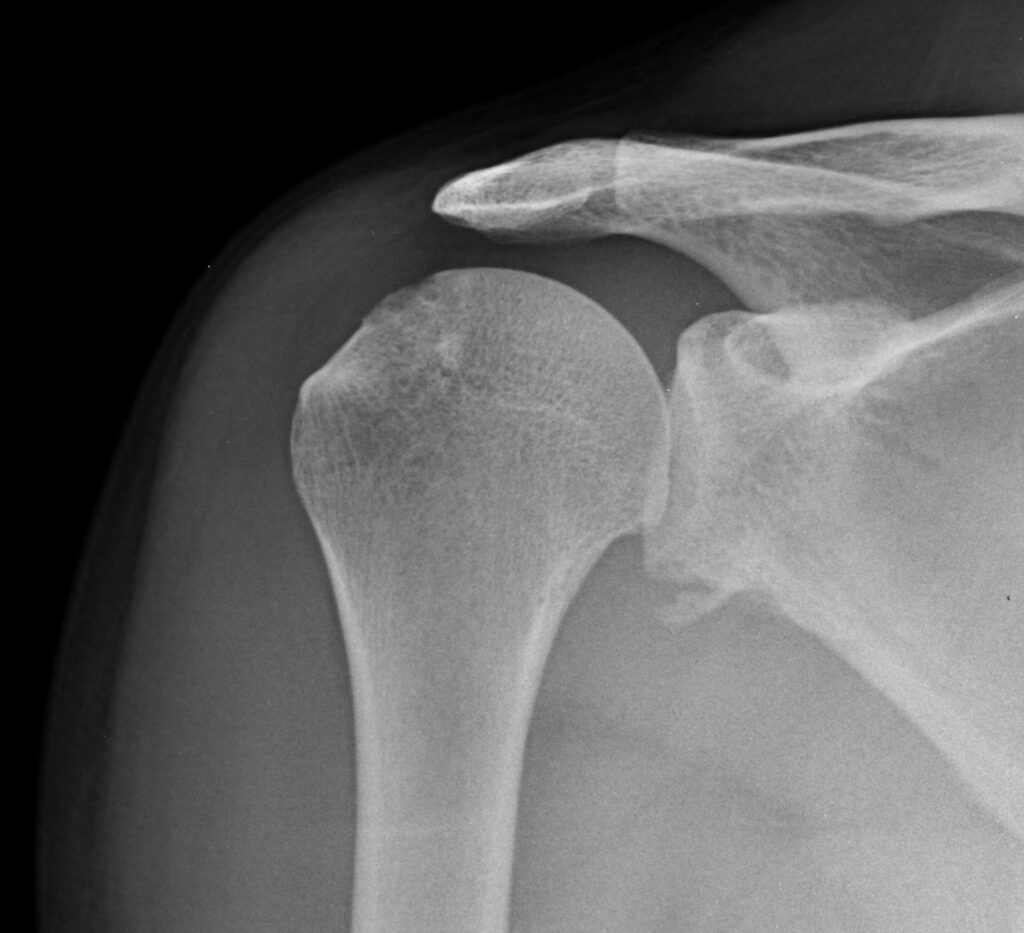

Suggest X-ray following an acute dislocation

Shoulder Dislocation - Poster or Anterior Fracture

Choosing the right therapist starts with them being able to read your X-rays and then plan a treatment plan for you. The therapists at Action Rehab are experienced in assessing and reading X-rays.